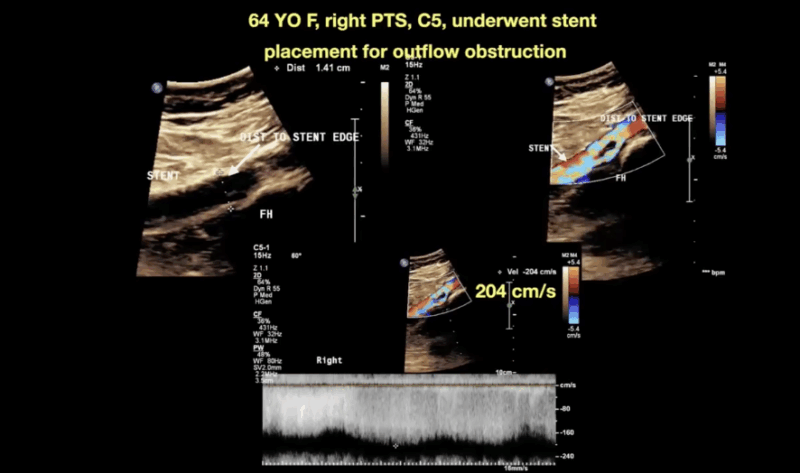

Here, we’re looking at a 64-year-old female with right-sided post-thrombotic changes (C5) and a healed venous ulcer.

She previously underwent stent placement for significant outflow obstruction — but the access site was positioned too high.

As a result, the true lesion was missed, leaving behind venous fibrosis and aliasing consistent with a high-grade venous stenosis (~200 cm/s).

Despite intervention, the patient remained symptomatic and ultimately required revision in the cath lab.

In this case, I’m demonstrating how to assess the diameter and velocity ratio — greater than 5 — which meets diagnostic criteria for left renal vein compression.

Optimize grayscale to clearly delineate anatomy.

Use calipers to measure both the maximally obstructed and dilated segments.

Advance your Doppler sample through the narrowest point to capture the peak velocity for an accurate ratio.